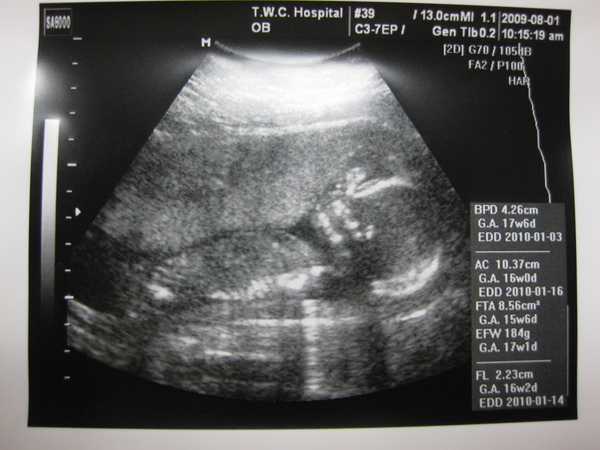

8/1去產檢了,

一切都很健康平安,

寶寶也開始長大了,從85g長到189g。

身體雖然有一點點小,但是一切都正常、平安。